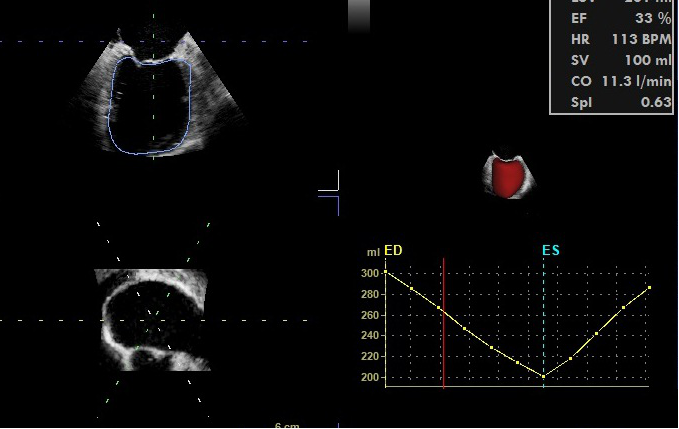

左心室有两条功能曲线(图7),容积-时间曲线和压力-时间曲线,左心室容积-时间曲线的最大值点对应着左心室舒张末容积,最小值点对应着左心室收缩末容积,最大值点和最小值点之间的差值反映每搏输出量(SV)。EF(射血分数)=SV/EDV。

图7左心室短轴切面与左心室容积/面积-时间曲线的关系

术中获得实时精确的LV容积-时间曲线尚不容易,需要用实时三维超声心动图技术、二维和三维图像自动分割技术(图8)、结合辛普森法计算得到,这种方法用在术中监测左心室的容积-时间曲线成本较高。如果心室形态正常,我们还是推荐用M型超声测量LVEDD/LVESD,计算FS(FS=LVEDD-LVESD/LVEDD)或者左心室中段短轴2D切面测量计算FAC=LVEDA-LVESA/LVEDA;EF≈2FS。

图8 3D-TEE获得左心室容积-时间曲线